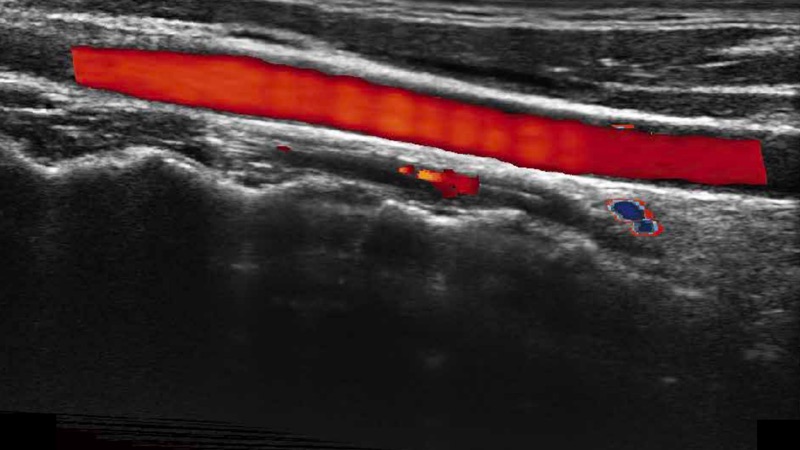

With the combination of color flow and real-time panoramic, visualizing the blood flow of an entire vein or artery is now an easy task. Accomplished in real-time for the convenience of the sonographers, any mistake can also be easily back tracked and corrected without interrupting the scan.